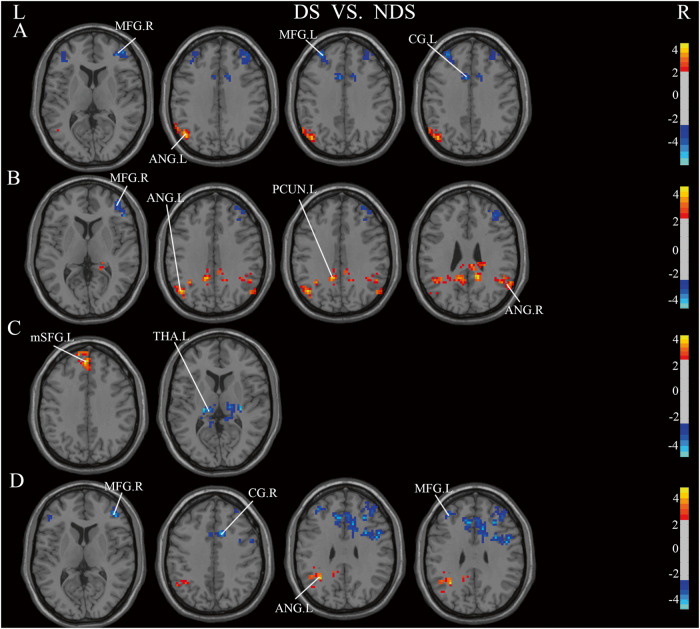

Functional connectivity

Analysis of FC was performed only in DS and NDS. The results of FC comparisons among DS, NDS are presented in Table S3–S10. When comparing NDS to DS, functional connectivity strengths between distinct brain regions, using the different brain regions in ALFF as seed points, the intensities of functional connectivity between ITG.L and Right Corpus Callosm, ITG.L and PCUN.R, ITG.L and STG.R, as well as PCUN.R and CG. R exhibited marked decreases in DS, Conversely, there were notable increases in functional connectivity strength observed in DS, particularly between PCUN.R and INS.R, as well as between PCUN.R and MFG.R. The different brain regions in ReHo were used as seed points, and the results suggested, DS demonstrated lower strength of functional connectivity between MFG.R and IFG.R compared to NDS (Fig. 5A–C). When employing expanded brain regions as the seed points, a marked increase in functional connectivity strength was observed within the DS between INS.L and ANG.L. Conversely, significant reductions were noted in connectivity between INS.L and MFG.R, INS.L and MFG.L, as well as INS.L and CG. L (Fig. 6A). When INS.R was used as the seed point, a significant reduction in functional connectivity strength was observed within the DS between INS.R and MFG.R. Conversely, there was a notable increase in functional connectivity strength between INS.R and ANG.R, INS.R and PCUN.L, as well as INS.R and ANG.L (Fig. 6B). In DS, the functional connectivity strength exhibited a significant decrease between PoCG.R and THA.L, ROL.R and MFG.R, ROL.R and CG.R, ROL.R and MFG.L, while it showed a notable increase between PoCG.R and mSFG.L, ROL.R and ANG.L (Fig. 6C, D).

Fig. 5. Significant Differences in functional connectivity between DS and NDS groups (GRF-corrected).

Significance level was set to voxel p < 0.01 with Gaussian random field correction for cluster p < 0.01, the color bars were t value. DS: deficit schizophrenia, NDS: non-deficit schizophrenia. L: left, R: right. A: with the left inferior temporal gyrus as the seed point, the significant different functional connections between DS and NDS, B: with the right precuneus as the seed point, the significant different functional connections between DS and NDS, C: with the right middle frontal gyrus as the seed point, the significant different functional connections between DS and NDS. Red and blue respectively represent regions where DS had higher and lower strength of functional connectivity compared to NDS.

Fig. 6. Significant Differences in functional connections between DS and NDS groups (GRF-corrected).

Significance level was set to voxel p < 0.01 with Gaussian random field correction for cluster p < 0.01, the color bars were t value. DS: deficit schizophrenia, NDS: non-deficit schizophrenia. L: left, R: right. A: with the left insula as the seed point, the difference between DS and HC, B: with the right insula as the seed point, the difference between NDS and HC, C: with the right postcentral as the seed point, the difference between DS and NDS, D: with the right rolandic operculum as the seed point, the difference between DS and NDS. Red and blue respectively represent regions where DS had higher and lower strength of functional connectivity compared to NDS.